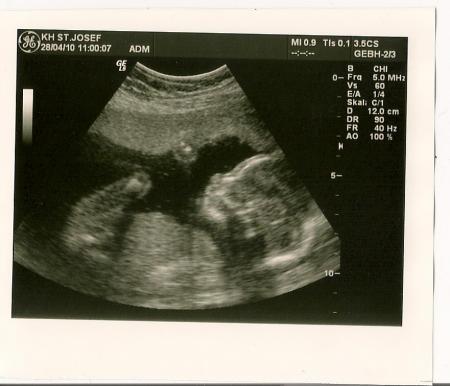

bin vom organscreening zurück. alles perfekt ;) ich habe mir sorgen gemacht weil mein würmchen immer etwas zu klein ist, aber passt alles genau zur ssw. danach war ich so im glücksrausch, oder keine ahnung, was das war, dass ich gleich mal zum ikea gefahren bin zum babyshopping ;) übrings spinnt unsere waage öfter mal und ich habe mich nachdem mein freund sich drauf gestellt hat, nochmal gewogen und da hatte ich nur 10dag mehr als bei meinem letzten FA-besuch ;) aber wegen der verstopfung, mir kommt vor, umso mehr ich versuche (joghurt, leinsamen, usw.) umso schlimmer wirds. langsam weiß ich nicht mehr weiter. es geht echt schon so weit, dass ich eifersüchtig bin wenn mein freund länger am klo ist hahaha lg

Bild zu